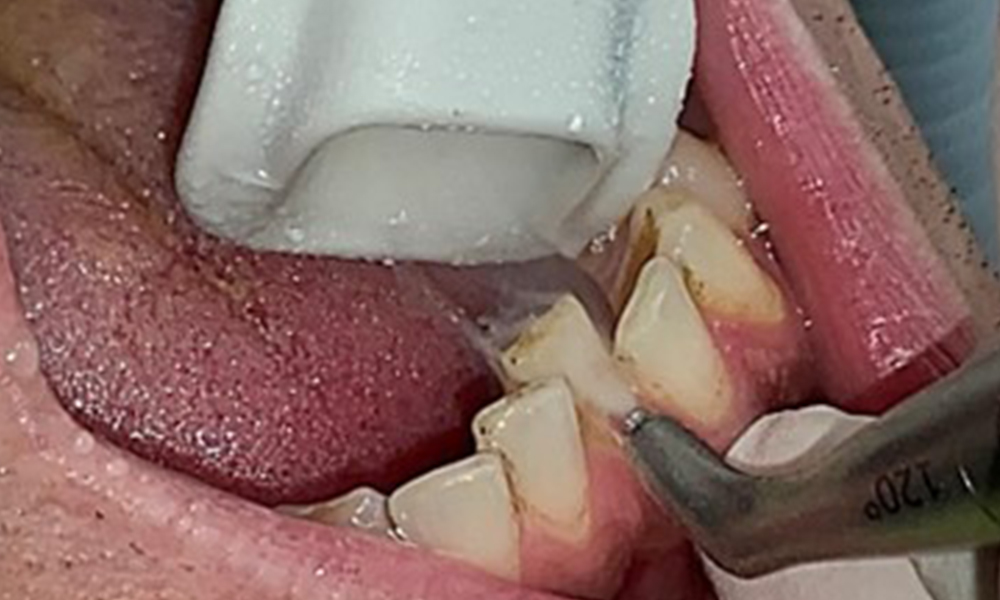

In der Instrumentierung der Therapiesitzung ergeben sich bezüglich der Methodenwahl aufgrund des gesunden Allgemeinzustandes des Patienten keine Einschränkungen. Gegebenenfalls ist in der Allergiephase individuell abzuklären, ob der Patient Einschränkungen beim Atmen hat. In diesem Fall ist abzuwägen, ob das Pulverstrahlgerät zum Einsatz kommen sollte.

Ziel ist es durch supra- und subgingivale Biofilmentfernung das Erkrankungsrisiko zu kontrollieren. Die Wahl der Instrumente erfolgt

bedarfsgerecht. Zunächst sind Zahnstein und ggf. Konkremente mit Ultraschall und / oder Handinstrumenten zu entfernen (Abb. 10).

Anwendung eines piezobetriebenen Ultraschallgerätes in Rg 36

Abb. 10 Anwendung eines piezobetriebenen Ultraschallgerätes in Rg 36 lingual (hier Proxeo Ultra, Firma W&H), © Dr. R. Krapf